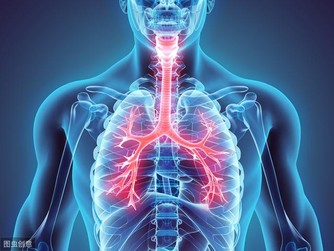

6、清除肺內毒素

人們每天除了會呼吸氧氣之外,還會吸過多的灰塵及細菌進入人的肺部,長期之後肺部會有諸多的毒素,毒素不但危害人體的健康,而且還會加速衰老,這時清除肺毒是有必要的。

每天早上或者晚上到環境較好的地方進行深呼吸,這樣可以使大量的新鮮空氣進入肺部,清除血液內毒素及自由基。從而達到清除肺部毒素的作用,延緩人體衰老。